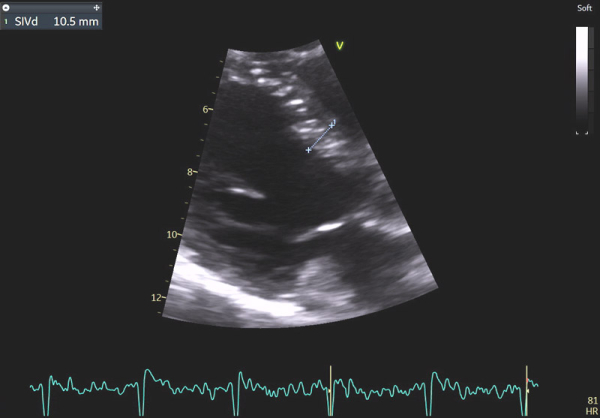

Image 2 : échocardiographie 2D en incidence parasternale grand axe : mesure du septum inter-ventriculaire

En effet, c’était le diagnostic à éliminer en priorité devant les symptômes présentés par la patiente avec un ECG légèrement microvolté et des éléments évocateurs d’une amylose cardiaque à l’échocardiographie : hypertrophie VG très minime mais > 10 mm chez une femme (> 11 mm chez un homme) (cf Vidéo 1 et Image 1), hypertrophie VD à 6 mm (>5 mm) (cf Image 9) et l’altération des strains longitudinaux basaux à l’AFI après valeurs préservées à l’apex (cf Image 7).